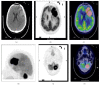

Primary Central Nervous System Lymphoma (PCNSL) is a rare neoplasm that can involve brain, eye, leptomeninges, and rarely spinal cord. PCNSL lesions most typically enhance homogeneously on T1-weighted magnetic resonance imaging (MRI) and appear T2-hypointense, but high variability in MRI features is commonly encountered. Neurological symptoms and MRI findings may mimic high grade gliomas (HGGs), tumefactive demyelinating lesions (TDLs), or infectious and granulomatous diseases. Advanced MRI techniques (MR diffusion, spectroscopy, and perfusion) and metabolic imaging, such as Fluorodeoxyglucose Positron Emission Tomography (FDG-PET) or amino acid PET (usually employing methionine), may be useful in distinguishing these different entities and monitoring the disease course. Moreover, emerging data suggest a role for cerebrospinal fluid (CSF) markers in predicting prognosis and response to treatments. In this review, we will address the challenges in PCNSL diagnosis, assessment of response to treatments, and evaluation of potential neurotoxicity related to chemotherapy and radiotherapy.